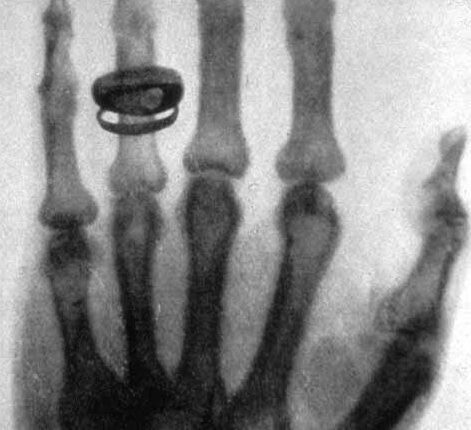

قام وليام رونتجن، مكتشف الأشعة السينية، بتسليط شعاع إلكتروني داخل أنبوب زجاجي مطبق بين طرفيه توتر كهربائي مرتفع. كان هذا الأنبوب مفرغ من الهواء وتنطلق بداخله إلكترونات من قطب كهربائي سالب إلى قطب كهربائي موجب. أُحيط هذا الإنبوب بورق ذو لون فاتح لحماية المستخدم من المجال الكهرمغناطيسي المنبعث ووُضعت شاشة فسفورية في نهايته. عندما اصطدم الشعاع الإلكتروني بالشاشة بدأت بالتوهج. عندما وضع ريتشارد رونتجن يده بالصدفة بين الأنبوب والشاشة الفسفورية، شاهد صورة لعظام يده على الشاشة، وكانت هذه أول عملية تصوير بالأشعة السينية.